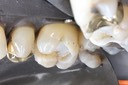

Bryan Sato #2 finish